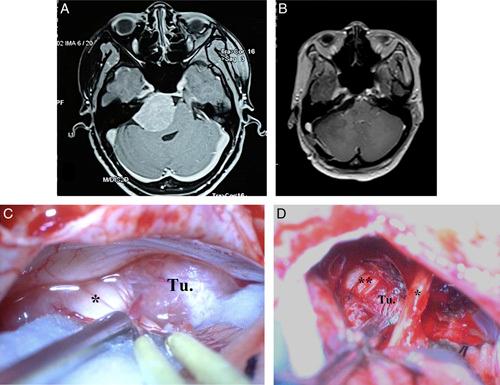

Cerebellopontine angle (CPA) meningiomas are the second most common tumor of the CPA. Depending on the site of dural attachment, the relationship between the tumor and critical neurovascular structures of the CPA is variable. This study aims to evaluate the influence of CPA meningioma location in relation to the internal auditory canal (IAC) on clinical symptoms, radiological presentations, and surgical treatments and outcomes which has been rarely reported in Vietnam.

A prospective study on 33 patients treated with microsurgery from August 2020 to May 2022 at the Neurosurgery Center, Viet Duc University Hospital.

The mean age of 27 females (85%) and 6 (15%) males was 54±12 years. Based on their location to the IAC, there were 16 premeatal cases (49%) (anterior to the IAC) and 17 retromeatal cases (15%) (posterior to the IAC). The time of diagnosis of the retromeatal group was later (16.5 vs. 9.7 months), the average tumor size of the 2 groups was not different, but when there was brainstem compression, the average tumor size of retromeatal group was larger (49 vs. 44 mm). The clinical presentations of the retromeatal group were related to the cerebellar symptoms, while trigeminal neuropathy symptoms all came from the premeatal group. Gross total resection of the premeatal group was 31% and of the retrometal group was 71%. The results of preserving the facial nerve function of the premeatal group were lower (44 vs. 82%). Postoperative Karnofsky score of the retromeatal group improved, while the premeatal group did not change.

Classification of CPA meningiomas according to their location to the IAC plays an important role in diagnosis and treatment, affecting clinical symptoms, surgical strategy as well as surgical outcomes.

桥小脑角(CPA)脑膜瘤是CPA区第二常见的肿瘤。根据硬脑膜附着部位,肿瘤与CPA区关键神经血管结构的关系各不相同。本研究旨在评估CPA脑膜瘤相对于内耳道(IAC)的位置对临床症状、影像学表现、手术治疗及预后的影响,而这在越南鲜有报道。

对2020年8月至2022年5月在越德大学医院神经外科中心接受显微手术治疗的33例患者进行前瞻性研究。

27例女性(85%)和6例男性(15%)的平均年龄为54±12岁。根据其相对于IAC的位置,有16例耳前病例(49%)(IAC前方)和17例耳后病例(51%)(IAC后方)。耳后组的诊断时间较晚(16.5个月对9.7个月),两组的平均肿瘤大小无差异,但当出现脑干受压时,耳后组的平均肿瘤大小更大(49 mm对44 mm)。耳后组的临床表现与小脑症状相关,而三叉神经病变症状均来自耳前组。耳前组的全切率为31%,耳后组为71%。耳前组保留面神经功能的结果较低(44%对82%)。耳后组术后卡诺夫斯基评分提高,而耳前组无变化。

根据CPA脑膜瘤相对于IAC的位置进行分类在诊断和治疗中起着重要作用,影响临床症状、手术策略以及手术预后。